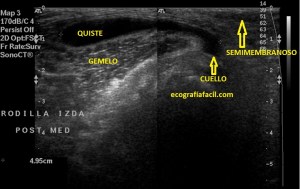

En la imagen 3 ves una imagen de un lipoma, mide 7 cms, la huella de la sonda mide 5cms, la «panoramic view» posee una regla centimetrada que sigue el contorno de la imagen, justo en la profundidad de la misma y lo marca la flecha amarilla. La profundidad la marca la flecha roja y la flecha blanca marca el rango centimetral de los 5cms, fíjate que la línea blanca es ligeramente mayor cada 5 cms. Sirve de referencia, como en la imagen 4 donde ves una colección en el glúteo de más de 10 cms.

Podemos medir valores superiores a los 15cms con alta calidad de imagen…podemos llegar a medir valores por encima de los 25 cms…es verdad que no todos los equipos tienen este ajuste ecográfico, es decir, es una aplicación y por tanto hay que pagarla.